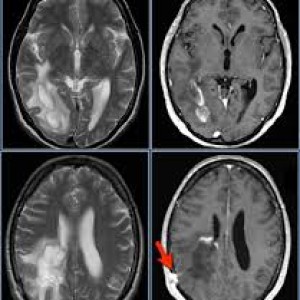

تشخیص بیماری احتیاج به آزمایشهای مختلفی دارد. گاهی اوقات تشخیص قطعی ممکن است ماهها طول بکشد که در این صورت باید با شکیبایی به انجام آزمایشات و دستورات پزشکی عمل کرد. در تشخیص بیماری ام اس و درمان آن باید به پزشک اعتماد کنید و روند مستمر درمان را پیگیری فرمایید.